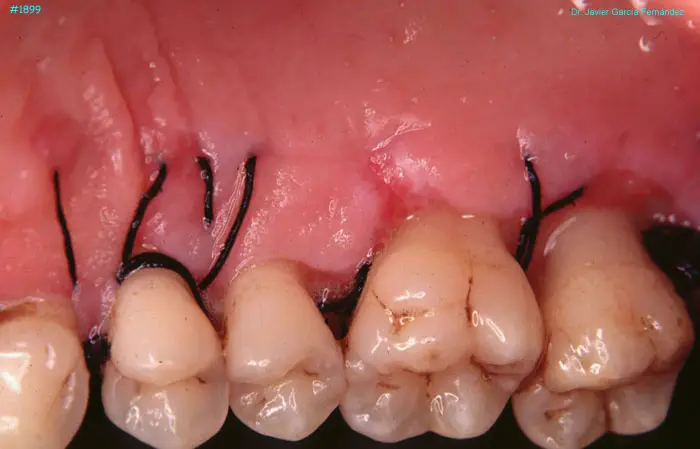

image 45